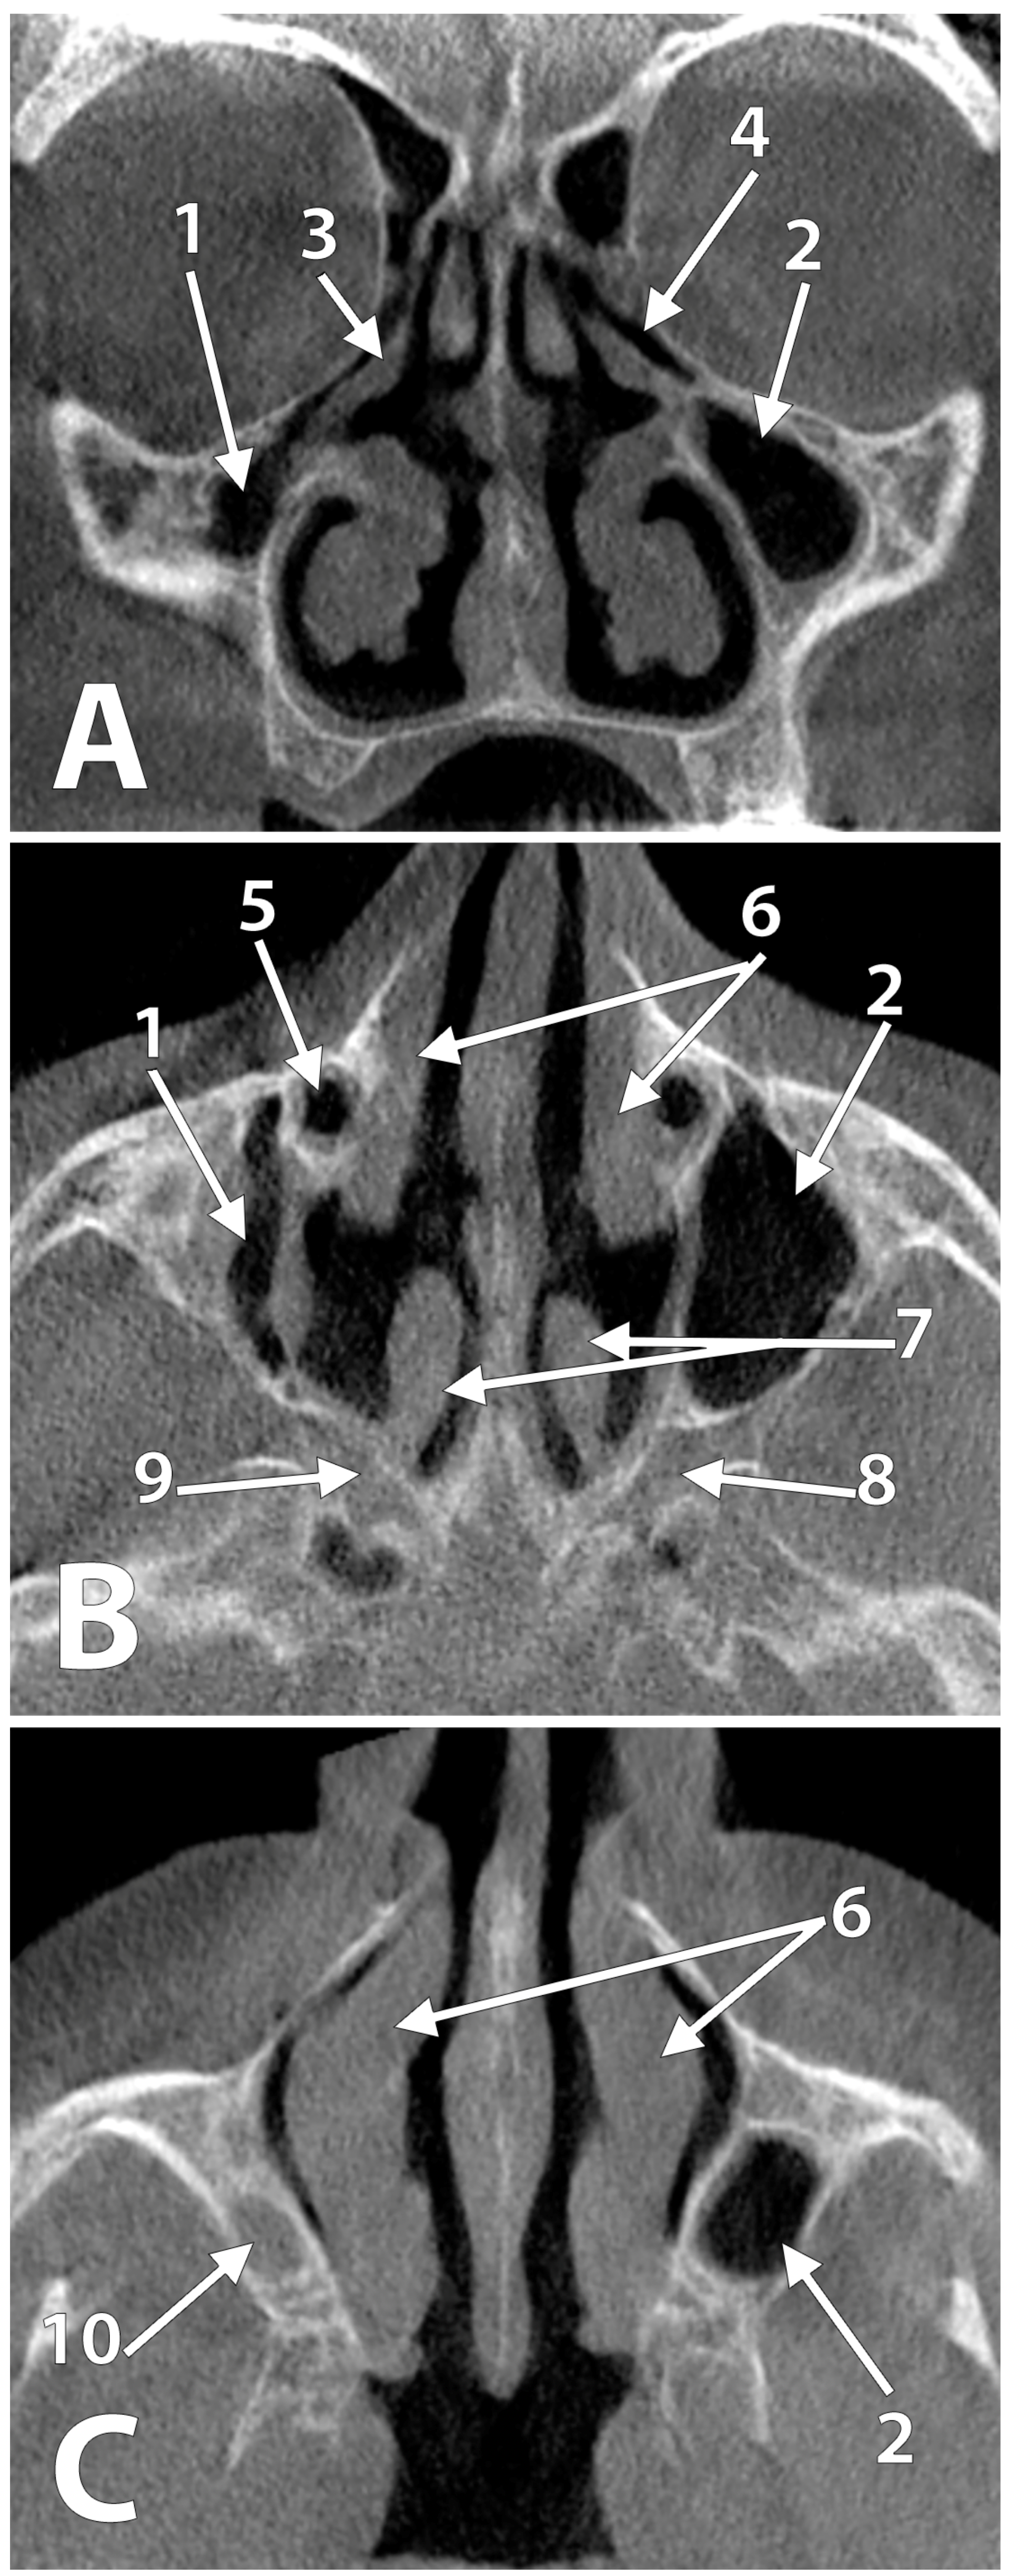

3. Results